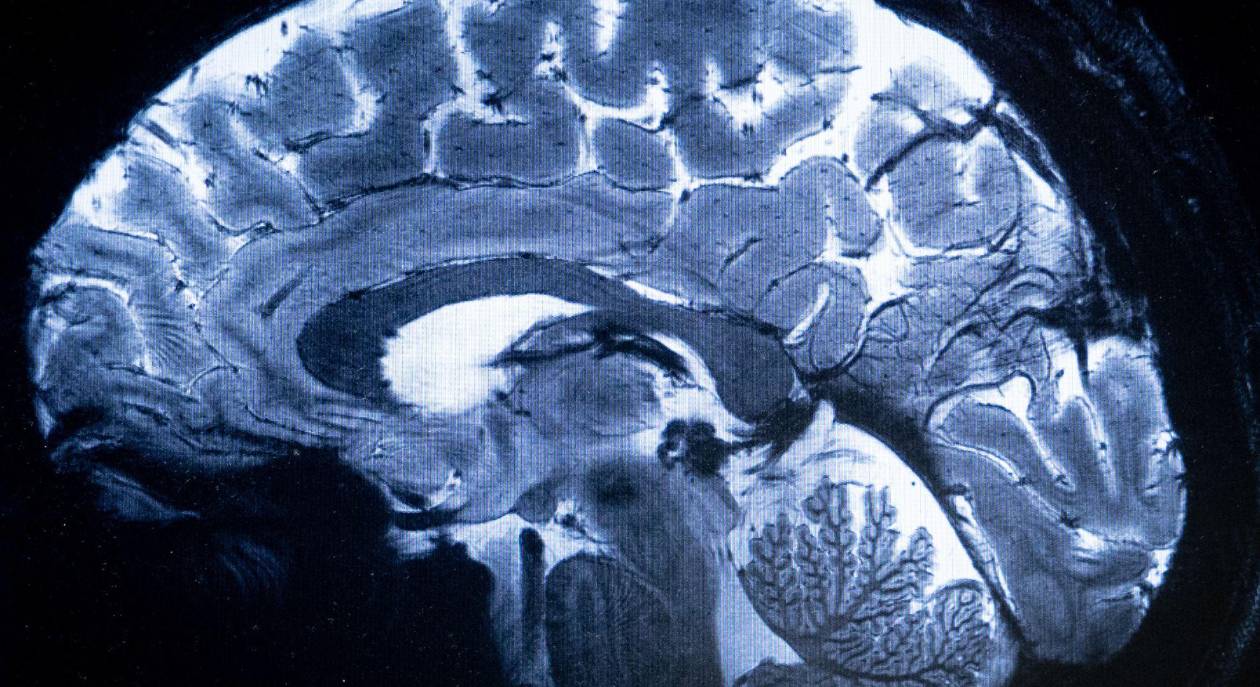

Los neurólogos en seis centros de investigación pidieron a 241 pacientes que no respondían que pasaran varios minutos seguidos realizando complejas tareas cognitivas, como imaginarse jugando tenis. El veinticinco por ciento de ellos respondió con los mismos patrones de actividad cerebral observados en personas sanas, sugiriendo que eran capaces de pensar y estaban al menos algo conscientes.

A partir de fines de la década de 1990, Schiff y sus colegas realizaron escaneos detallados del cerebro de pacientes con trastornos de la conciencia. Si bien muchos tenían daño masivo, otros tenían franjas sorprendentemente grandes de tejido intacto. Los neurólogos se preguntaban si al menos algunos de los pacientes todavía estaban “allí adentro” —y simplemente no podían avisar a nadie de ello.

En un estudio en el 2006, Adrian Owen, entonces en la Unidad de Ciencias del Cerebro y Cognición del Consejo de Investigación Médica, en Cambridge, Inglaterra, y sus colegas pidieron a una mujer diagnosticada en estado vegetativo que se imaginara jugando tenis. En respuesta, regiones de su cerebro se activaron, las mismas regiones que se activan en cerebros sin daño.

Su análisis reveló que 60 pacientes mostraron señales de conciencia en resonancias magnéticas funcionales, registros de electrodos o ambas cosas.